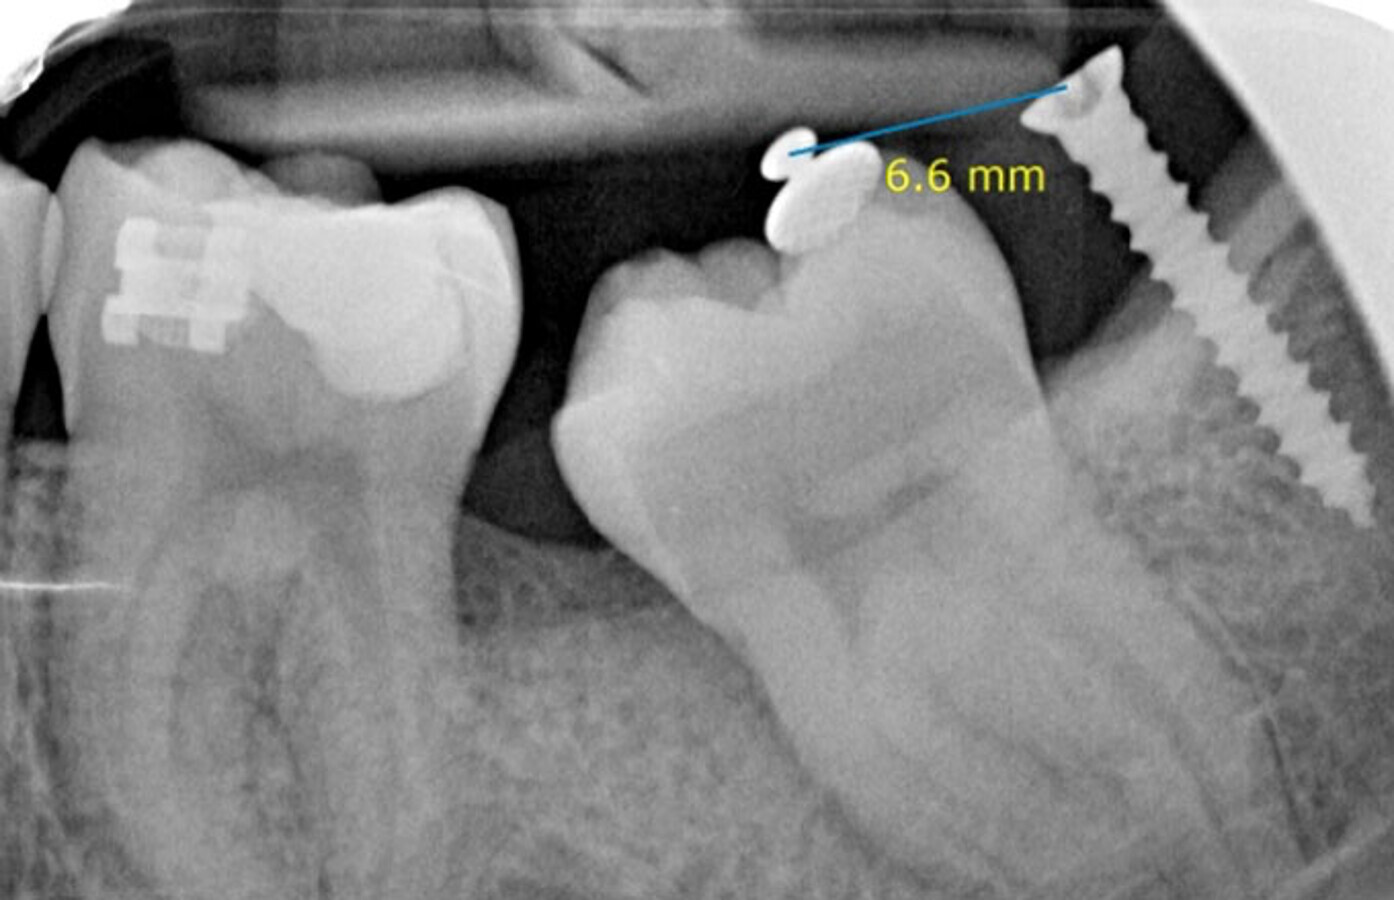

Control coil spring abierto (diente 38 exodonciado).

El tratamiento ortodóntico comienza inmediatamente a la exodoncia del cordal. Como la formación de la raíz del segundo molar es completa, no se endereza quirúrgicamente (luxación). Se desimpacta parcialmente el segundo molar por medio de un coil spring abierto y un seccional NiTi de 34 a 37. Mientras tanto, va cicatrizando el alveolo y la ostectomía realizada para extraer el diente 38.